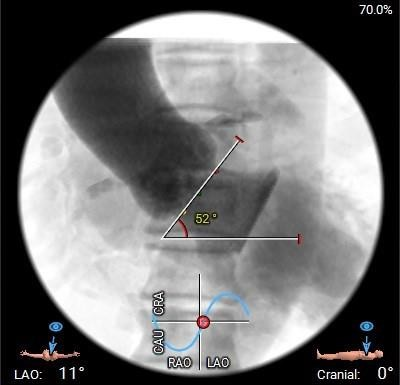

•瓣环水平夹角约52°,非横位心 ,主动脉弓宽度、角度尚可,弓顶部有明显附壁钙化。

工作位造影